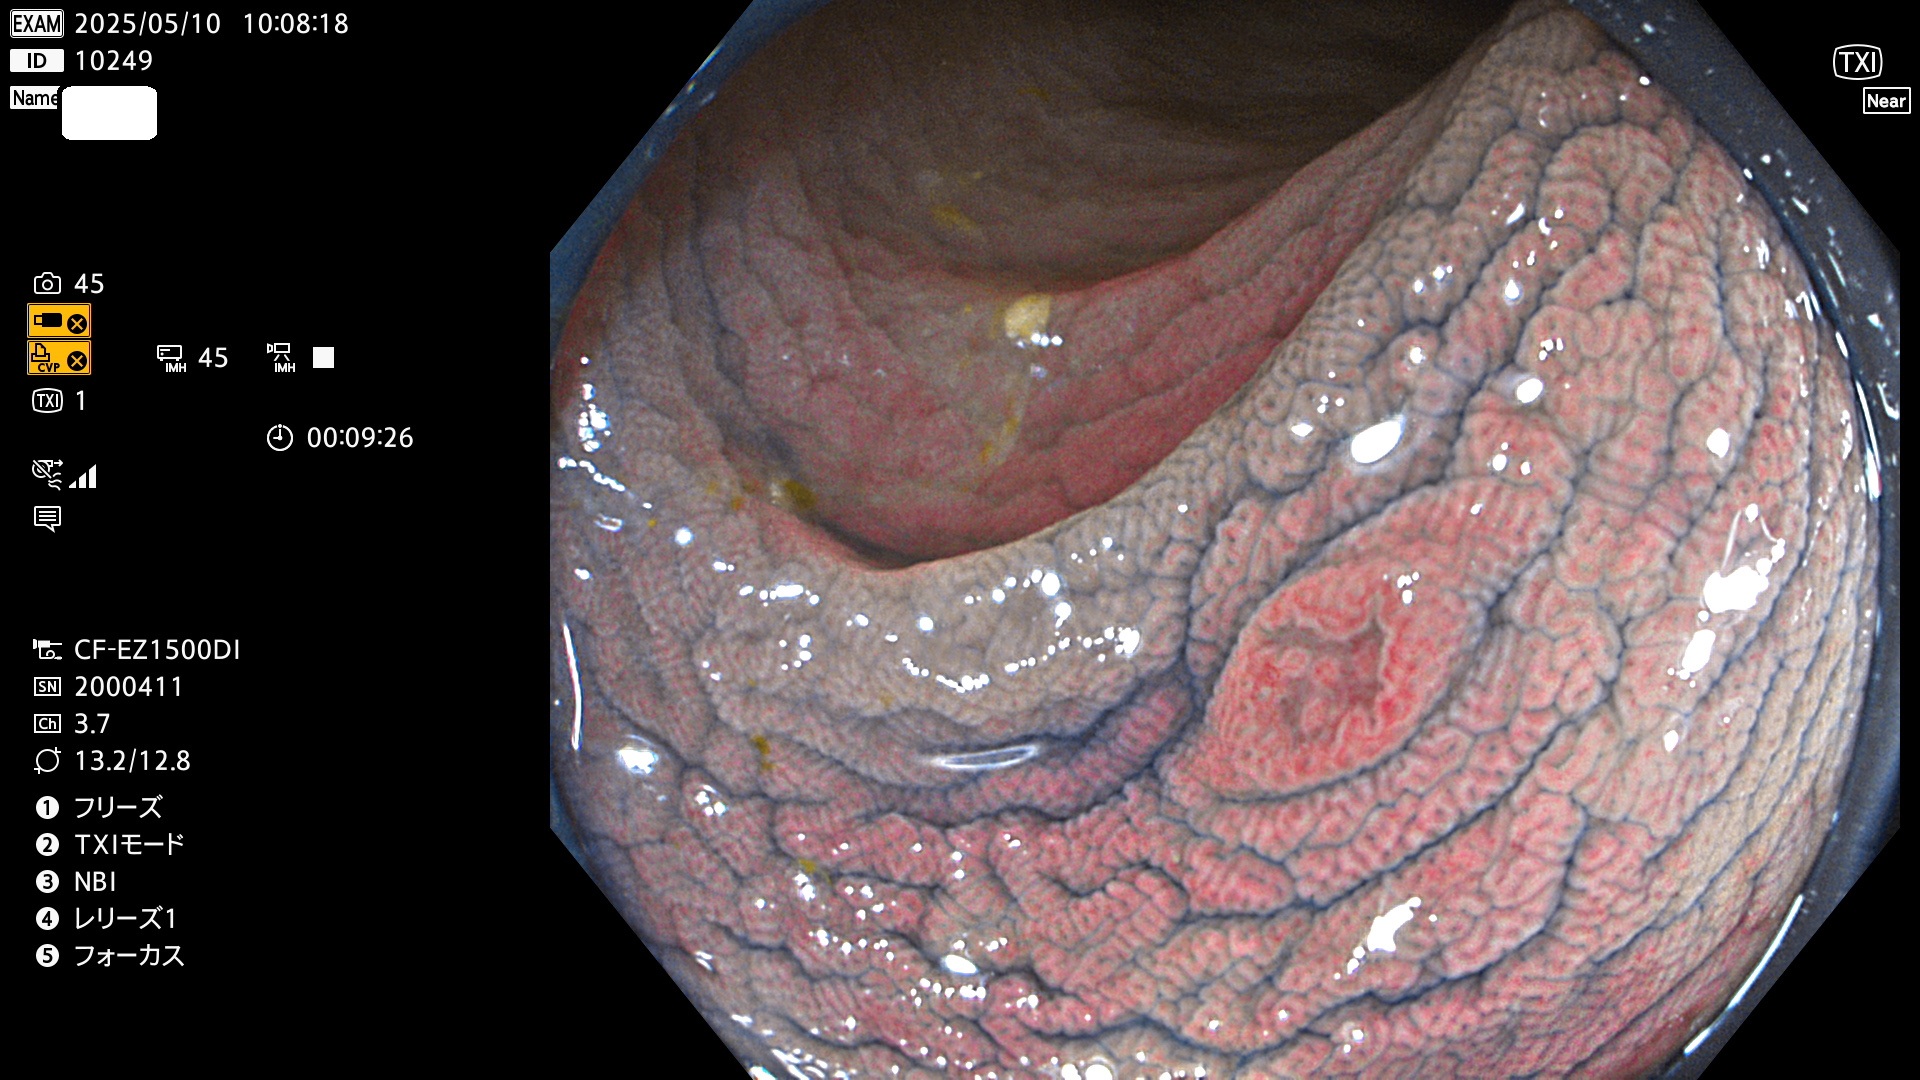

今週のUb、Uc型腺腫

完全に平坦な物をUb、陥凹している物をUcと呼びます。Ubは認識が困難で、Ucはびらん(炎症)と紛らわしいために見落とされやすく、「内視鏡後・大腸癌」の原因になります。

抽出の対象期間 2025年5月8日〜5月11日の4日間(48件の検査)14個 (14/48=29%)